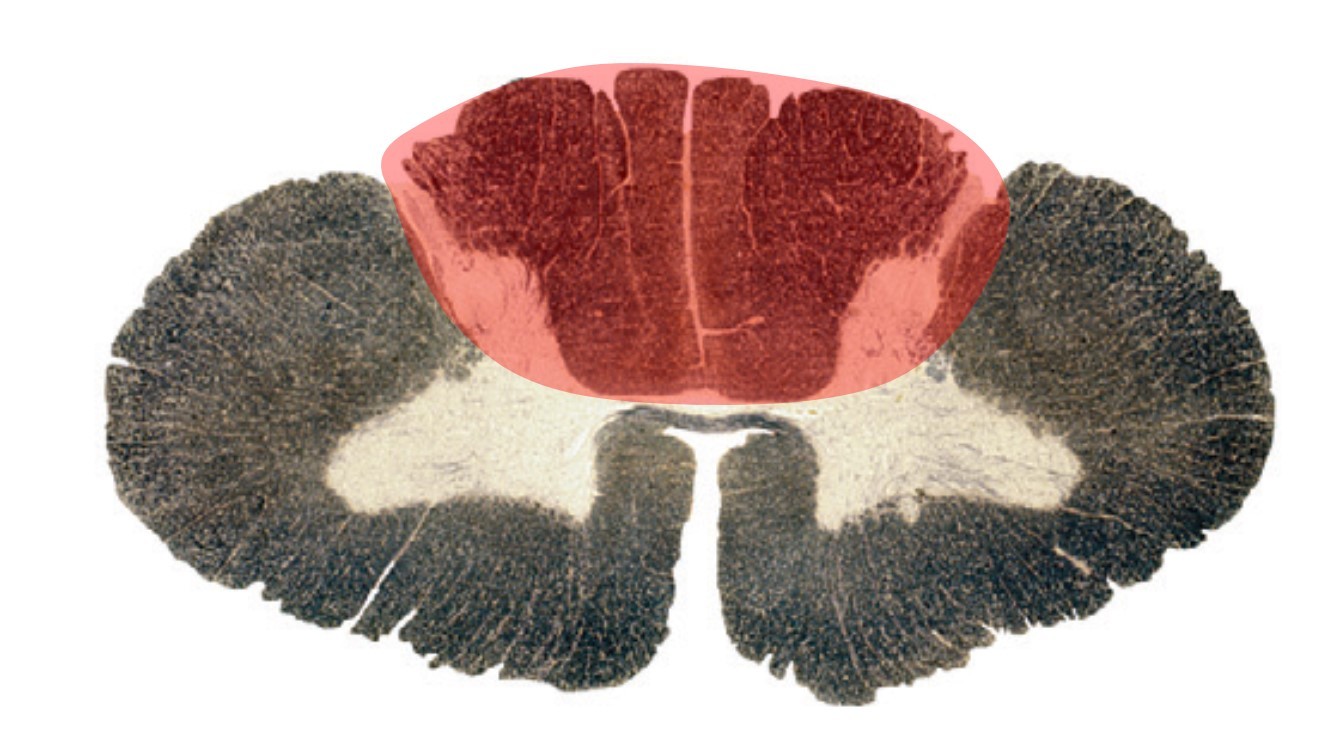

The region highlighted corresponds to the territory of which artery/pair of arteries?

Anterior spinal

Medullary

Posterior spinal

Vertebral